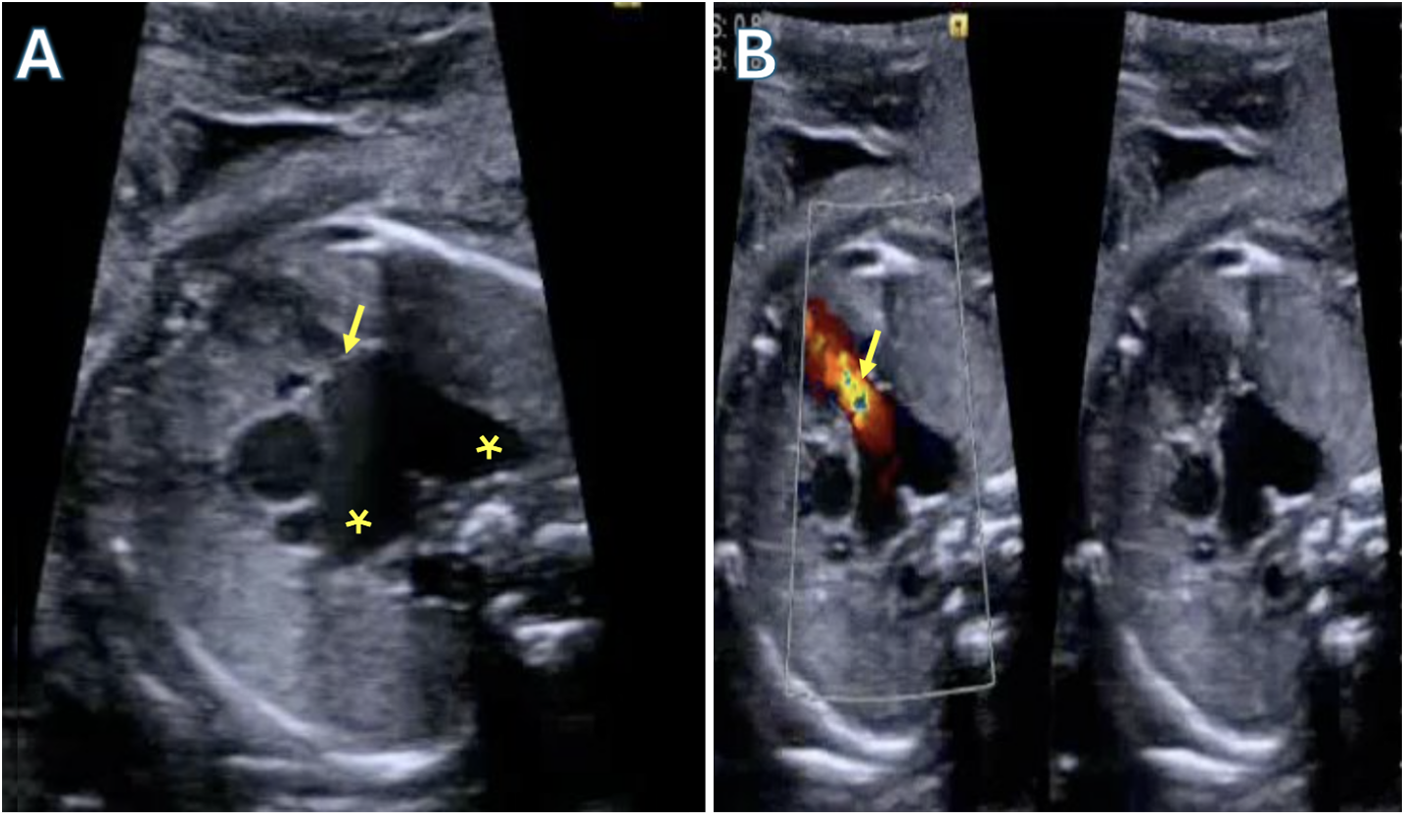

Tetralogy with absent pulmonary valve is a rare form of Tetralogy (<5% of cases) in which a pulmonary annular ring creates fixed obstruction to right ventricular outflow. It is believed that the absence of a valve leads to back-and-forth flow from the right ventricle into the pulmonary artery leading to aneurysmal dilation of the main PA and branch pulmonary arteries sometimes extending to the hilum as seen in Fig. 8. Z-scores of the arteries are frequently greater than +2 or 3. The pulmonary vessels show a wide spectrum of anatomical variation. In milder cases, a patent Ductus Arteriosus (PDA) is present alongside well-developed pulmonary arteries. However, in most cases no PDA is present resulting in diminutive or missing vessels with Pulmonary circulation supported via major aorto-pulmonary collateral arteries (MAPCAs) originating from the aorta as seen in Fig. 9. Although the right ventricle is hypertrophied there is usually no dynamic sub-annular obstruction as the infundibulum frequently is dilated without stenosis. Associated abnormalities include tracheo- and bronchomalacia leading to respiratory abnormalities including hyper inflated lungs and air trapping [74]. Patients present in two groups, those with early symptoms, and those without. Early presenters have cyanosis mostly driven by respiratory distress and regularly need mechanical ventilation and urgent surgery. In some instances, mechanical ventilation can be augmented (or avoided) with placing the baby prone to relieve obstruction.

Figure 8: Fetal echocardiogram demonstrating Tetralogy of Fallot with absent pulmonary valves. A: Severe dilated branch pulmonary arteries (asterisks) with a rudimentary pulmonary valve (arrow). B: Color compare showing severe regurgitation through the rudimentary pulmonary valve (arrow)